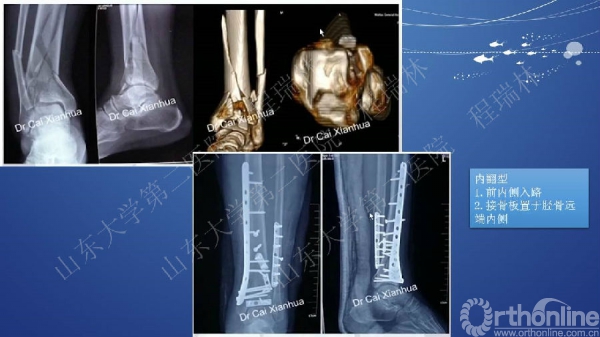

Pilon骨折的手术基本原则

Pilon骨折是踝部的复杂骨折,以高能量损伤、不稳定、软组织损伤严重为特点。手术复杂,并发症常见且严重。一旦治疗失败,常常带来灾难性的后果,如截肢、严重创伤性关节炎后期再关节融合等。

Pilon骨折的治疗目的:软组织保护,恢复下肢力线,解剖复位关节面。